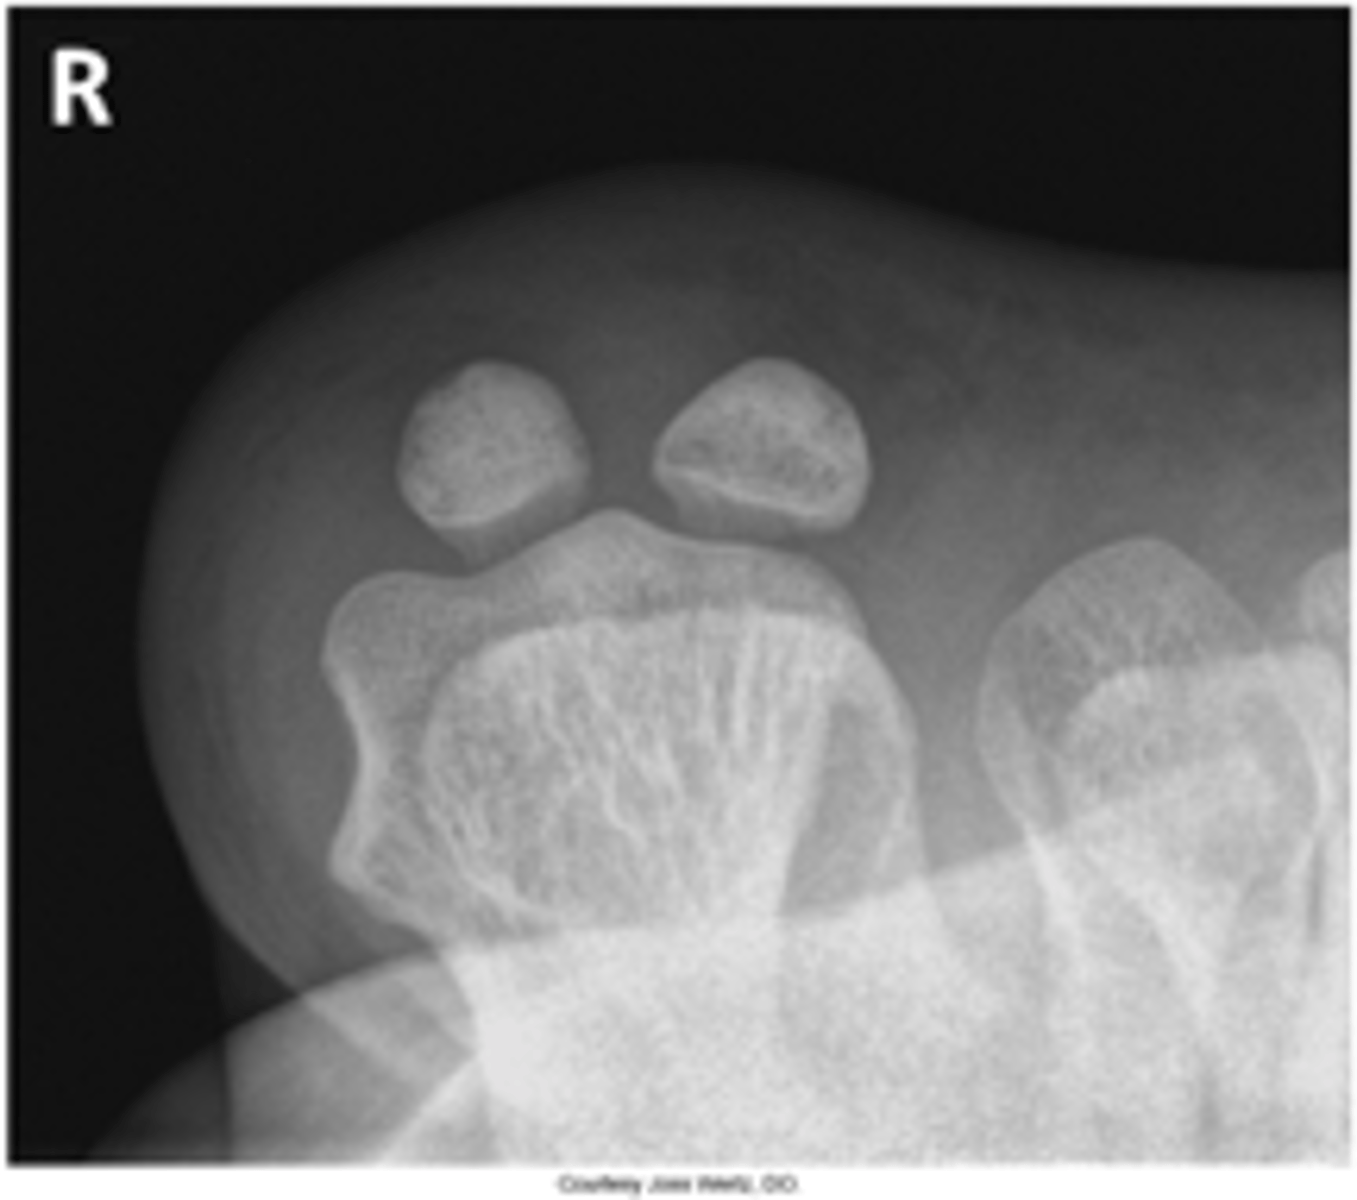

Tangential Sesamoids Supine

What projection is this?

Evaluation Criteria for Tangential Sesamoids

- Sesamoids free of superimposition

- Minimum of three metatarsals seen

- Optimal exposure factors